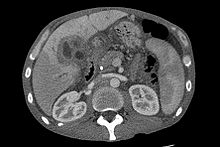

Ultrasound of the liver and biliary tree is often used as the initial imaging modality in people with suspected obstructive jaundice.[48][49] Ultrasound can identify obstruction and ductal dilatation and, in some cases, may be sufficient to diagnose cholangiocarcinoma.[50] Computed tomography (CT) scanning may also play an important role in the diagnosis of cholangiocarcinoma.[51][52][53]